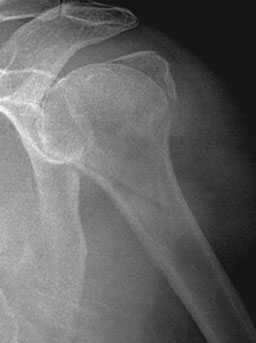

Рис. 1. На рентгенограммах: оскольчатый перелом проксимального отдела плечевой кости со смещением отломков.

Переломы проксимального отдела плечевой кости расположены проксимальнее хирургической шейки кости (см. рисунок Основные анатомические ориентиры в проксимальном отделе плечевой кости Основные анатомические ориентиры в проксимальном отделе плечевой кости ). Большинство из них сопровождаются минимальными смещением и поворотом отломков. Диагноз устанавливают по данным обзорной рентгенографии или, иногда, КТ. Большинство из этих переломов можно лечить наложением повязки, пращевидной повязки, с ранней мобилизацией.

Перелом хирургической шейки плечевой кости.

Переломы проксимального отдела плеча возникают при прямом ударе по наружной поверхности плечевого сустава, либо при падении на локоть или кисть. Среди переломов проксимального конца плечевой кости наиболее часто встречаются переломы хирургической шейки. Частые переломы в данной области объясняются тем, что кортикальный слой этого участка плечевой кисти тоньше, и хирургическая шейка является местом перехода фиксированной части плеча (места прикрепления мышц, связок) в менее фиксированную.